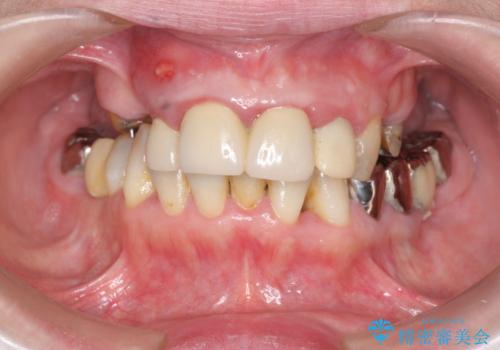

多発した虫歯による咬合崩壊 インプラントを用いた全顎治療

- 「これまで歯の治療をおざなりにしてしまい本当に後悔している。 時間と費用がかかってもいいので、しっかりと安心してかめるような状態にしてほしい。」、と全体的な治療を希望され来院されました。

歯の破折・再発した大きな虫歯・根尖病変・歯の欠損、これらの問題を根管治療・歯周外科・インプラント治療・セラミック補綴を行うことで一つづつ解決し安定した咬合状となるよう治療を進めます。